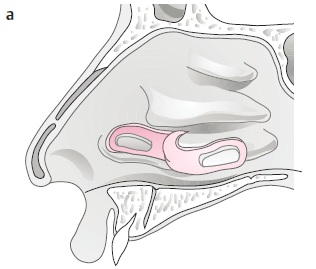

3. 手術方式(小洞): 如破損較小,可使用局部擴張或轉位(local flap),在內視鏡下以鼻中隔黏膜皮瓣或下鼻甲皮瓣修補。

4. 手術方式(大洞): 若破損較大,可考慮開放式鼻整形(Open rhinoplasty)修補,使用鼻道下方黏膜。

此方式為目前成功率最高的修補方式,也是最常使用的手術法。